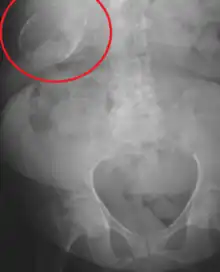

| Porcelain gallbladder on X-ray | |

Porcelain gallbladder is a calcification of the gallbladder believed to be brought on by excessive gallstones, although the exact cause is not clear. As with gallstone disease in general, this condition occurs mostly in overweight female patients of middle age. It is a morphological variant of chronic cholecystitis. Inflammatory scarring of the wall, combined with dystrophic calcification within the wall transforms the gallbladder into a porcelain-like vessel. Removal of the gallbladder (cholecystectomy) is the recommended treatment.

Abdominal radiography (X-ray), abdominal ultrasound or CT scan.